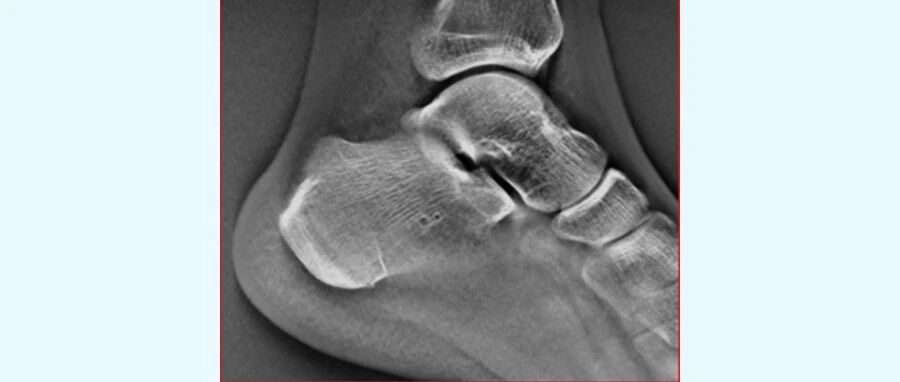

TOMOS 功能可以在一次扫描下,获得连续多层面的高清晰断层图像。 TOMOS 功能减少了因组织重叠造成的干扰,提高了病变检出的敏感性和特异性。即使是细微的骨折线,在它生成的清晰图像下,也能清晰呈现。

通过TOMOS,可见骨折线